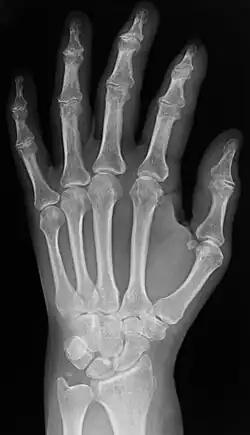

Two forms of radiographic images are in use in medical imaging. Projection radiography and fluoroscopy, with the latter being useful for catheter guidance. These 2D techniques are still in wide use despite the advance of 3D tomography due to the low cost, high resolution, and depending on the application, lower radiation dosages with 2D technique. This imaging modality uses a wide beam of X-rays for image acquisition and is the first imaging technique available in modern medicine.

- Projectional radiographs, more commonly known as X-rays, are often used to determine the type and extent of a fracture as well as for detecting pathological changes in the lungs. With the use of radio-opaque contrast media, such as barium, they can also be used to visualize the structure of the stomach and intestines – this can help diagnose ulcers or certain types of colon cancer.